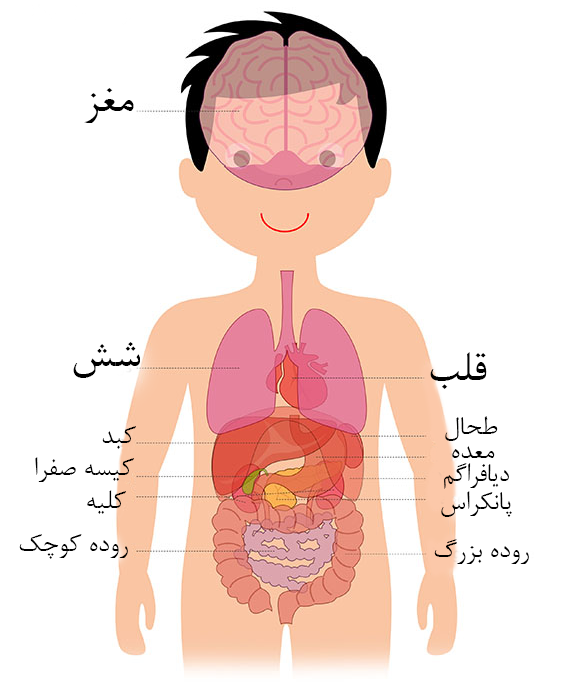

عکس داخل شکم انسان. در این همان طور که مشخص است شکم حالت بیضی شکل پیداکرده و این بیضی که کناره های شکم کشیده شده است. تعداد سلول های بدن انسان حدود ۳۷ ۲ تریلیون تخمین زده شده اند. Abdomen که در زبان عامه به غلط به آن دل نیز می گویند در آناتومی به قسمتی از تنه گفته می شود که مابین دیافراگم از بالا و سطح فوقانی لگن خاصره از پایین قرار دارد. ربات دیدنی ربات انساننمای چینی به صورت یک دختر جوان ساخته شده و جیا جیا نامگذاری شده است این ربات طوری برنامهریزی شده که میتواند صحبت کند و احساسات خود را از طریق تغییرات در چهره حالات.

شکل دوم شکم مادری را نشان می دهد که جنین دختر دارد. وحشت مادر از عکس سونوگرافی جنین داخل شکمش عکس. تصاویر جالب از داخل مغز و نخاع انسان آخرین نیوز. بدن انسان کل ساختار انسان است که سر گردن تنه سینه و شکم دو بازو و دست ها و دو ساق پا و پاها را شامل می شود.

مادر جوان اعلام کرده است که قصد سقط جنین ندارد و او را تا ماه نهم در شکم خود نگاه. درد شکم ناف درد شکم و معده علائم درد شکم سمت راست درمان درد شکم نفخ و درد شکم. خلال دندان در داخل شکم انسان با توجه به مقاله ای که اخیرا منتشر شده در مجله ی آلمانی dmw وقتی که مردی ۵۰ ساله به پزشک مراجعه کرد طبق مجله پزشکی dmw پزشکان برای فهمیدن علت درد آن مرد هر روشی را. عکس سونوگرافی جنین شبیه جمجمه انسان.